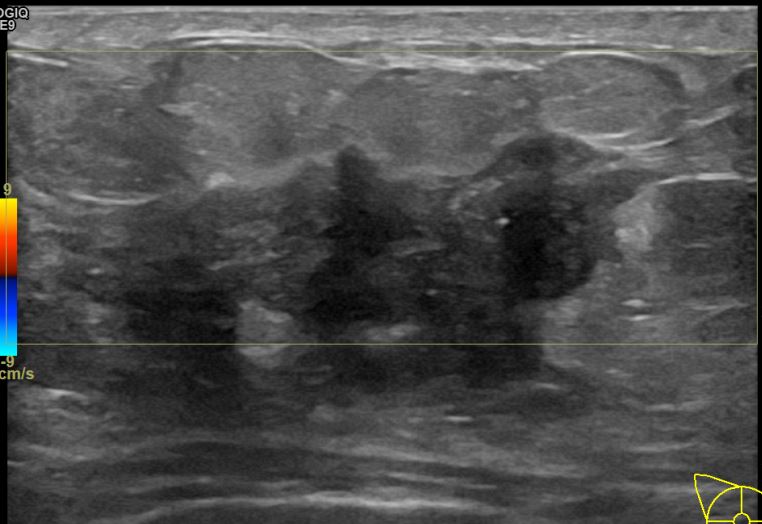

상기환자는 만져지는 멍울로 내원하신 40대초반

여성분으로 의심스러운 우측혹 조직검사 시행해 침윤성암으로 진단되었습니다